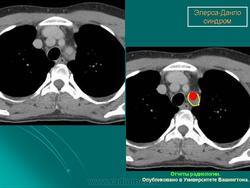

3. Васкулярный тип.

Наследуется по аутосомно-доминантному типу. Основные диагностические критерии: тонкая, прозрачная кожа, разрывы стенки артерий, кишечника и/или матки,обширные кровоизлияния, характерный фенотип. Дополнительные диагностические критерии: гипермобильность мелких суставов, разрыв сухожилий и мышц, косолапость, варикозное расширение вен с ранней манифестацией, артериовенозные каротидно-кавернозные фистулы, пневмоторакс/пневмогидроторакс, атрофия десневого края; положительный семейный анамнез, случаи внезапной смерти у близких родственников (многие пациенты не доживают до 50 лет из-за разрыва артерий или, что реже кишечника). Наличие двух и более главных критериев с большой вероятностью указывает на диагноз васкулярного типа СЭД и является показанием для лабораторной диагностики. Нередко отмечается характерный фенотип (узкий нос, тонкие губы, натянутая кожа, впавшие щеки и экзофтальм, обусловленный, в основном, снижением подкожно-жирового слоя). Надо отметить, что такой фенотип характерен для взрослых больных, а у детей он практически не выражен. Гипермобильность суставов обычно ограничена суставами пальцев. Максимальная частота спонтанных артериальных разрывов приходится на третью-четвертую декады жизни, но они могут возникать и раньше. Чаще всего вовлечены артерии среднего калибра. Беременность и роды могут осложняться разрывом матки и маточными кровотечениями, а также разрывом влагалища и промежности. Именно артериальные разрывы являются наиболее частой причиной внезапной смерти. Поэтому в качестве диагностических мероприятий рекомендуются, по возможности, неинвазивные процедуры. При этом типе СЭД сравнительно хорошо изучены изменения на молекулярно-белковом уровне. Этиологическим фактором являются мутации в гене коллагена IIIтипа.